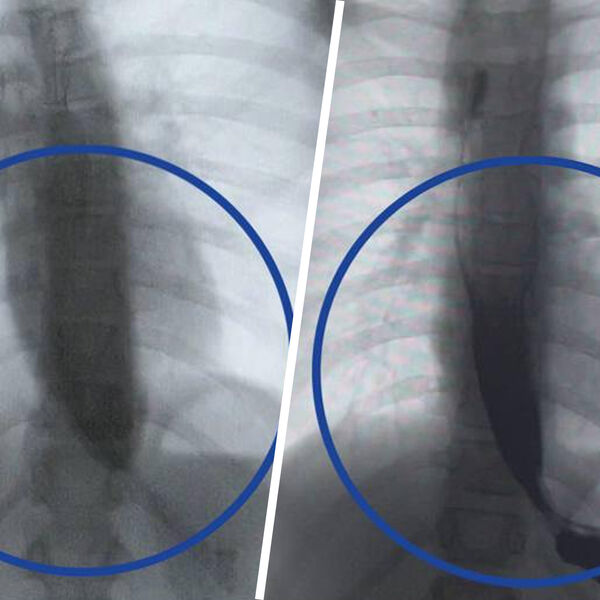

Врачи Детского клинического центра им. Л.М. Рошаля спасли девятилетнюю девочку с редким заболеванием — ахалазией кардии, из-за которого ее пищевод был расширен в пять раз. Об этом сообщили в пресс-службе минздрава Московской области.

Медики рассказали, что пищевод пациентки из-за патологии был расширен до четырех сантиметров, при норме в семь — десять миллиметров.

«Мы через разрез в пищеводе создали подслизистый туннель и рассекли циркулярные мышцы, блокирующие проход пищи», — поделился заведующий отделением эндоскопических методов диагностики больницы Александр Иноземцев.

Операция прошла успешно, что уже на следующий день показало контрастное исследование — пища стала беспрепятственно поступать в желудок.